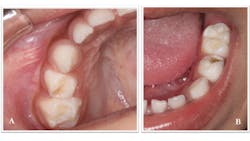

A three-year-old Hispanic male came to the clinic for his first dental visit. He was a well child without significant medical issues, and he regularly saw his pediatrician for well-child checks. The mother and patient denied any history of orofacial or dental symptoms, but mom was “concerned about a cavity in his bottom teeth.” The child was highly reactive to the dental environment and uncooperative for a knee-to-knee clinical exam. We were able to identify two carious lesions on the occlusal surfaces of the child's teeth—Nos. B and L (figure 1), but we were unable to obtain diagnostic radiographs.

Figure 1: Carious lesions noted on tooth No. B (shown in photo A) and tooth No. L (shown in photo B)